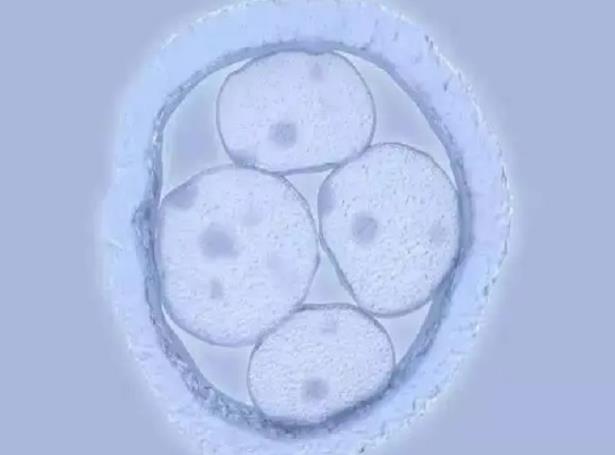

45歲之后,很多女性都處于圍絕經(jīng)期,卵巢內(nèi)可以利用的卵子很少。同時,隨著年齡增加,卵子質(zhì)量下降,受精后,發(fā)生染色體異常分裂的概率大大增加,相應(yīng)的,染色體異常的胚胎生成增加。數(shù)量和質(zhì)量都下降的情況下,胚胎著床率大大下降,臨床妊娠率<5%,接近為0,即使懷孕,出現(xiàn)胚胎停育的風(fēng)險也大大增加。